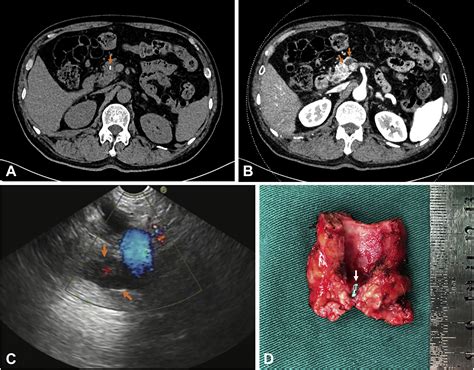

Because the pancreas is deep within the abdomen, doctors rely on advanced imaging techniques to visualize the ducts clearly. If you present with symptoms or if a routine ultrasound shows pancreatic duct dilation, your physician may order one or more of the following tests:

Endoscopic Ultrasound (EUS) Provides high-resolution images; allows for biopsy if a mass is suspected.

Computed Tomography (CT) Scan Useful for rapid assessment and identifying large masses or calcifications.

Endoscopic Retrograde Cholangiopancreatography (ERCP) Both diagnostic and therapeutic; allows for stone removal or stent placement.